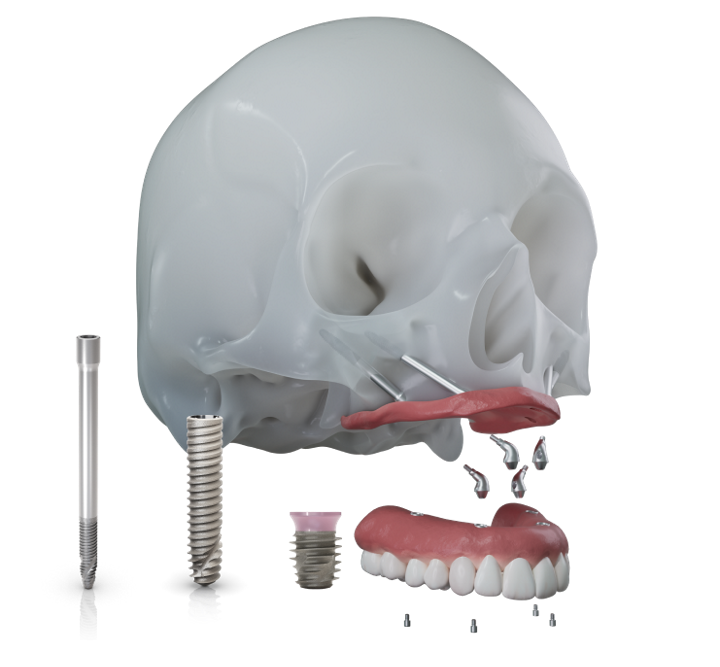

Soluciones para Atrofia Severa de la Maxila

Zygoma-S & GM®

Los implantes cigomáticos de Neodent® no solo proporcionan una solución de restauración inmediata, sino también una alternativa a los procedimientos de injerto óseo.

Diseñados para ofrecer estabilidad, previsibilidad del tratamiento, precisión y satisfacción del paciente, los implantes cigomáticos cuentan con un diseño versátil y una gama de longitudes adaptadas a la anatomía única del paciente y la salud del tejido.

Maxilar Severamente Atrófico

Tecnología del Sistema Grand Morse®

Soluciones NeoArch

Angulaciones MUA de 0º a 60º